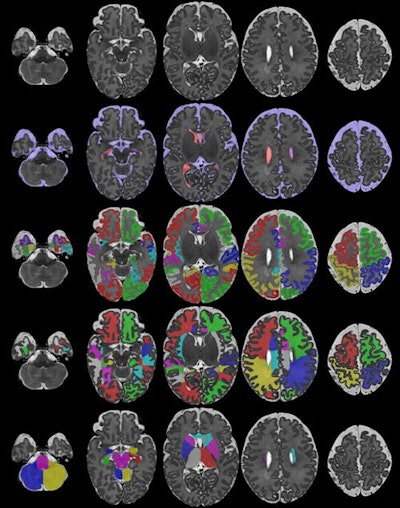

A: As part of my PhD, we are seeking to improve our understanding of how a baby's brain develops during the first few weeks of its life. In particular, we are trying to characterize the developmental trajectory of a healthy brain by applying AI to MRI scans of babies acquired via the developing Human Connectome Project (dHCP), led by KCL Imperial College and the University of Oxford. In my project, we are trying to create a "movie" of how a normal brain develops, but as we only have "snapshots" of different newborn babies at different ages, we first need to match similar anatomical areas of the human brain across all the different images and babies. It's challenging work, as the brain changes significantly during those vital first few weeks.

To achieve this goal, I am building a deep-learning framework that can take both structural and microstructural information of the brain and find these "anatomical correspondences" over time. By the end of my PhD in 2022, we hope to have a 4D model of brain development that can be used to detect abnormalities, predict developmental trajectories, and find if there are any anatomical regions in the brain that are important for normal development.